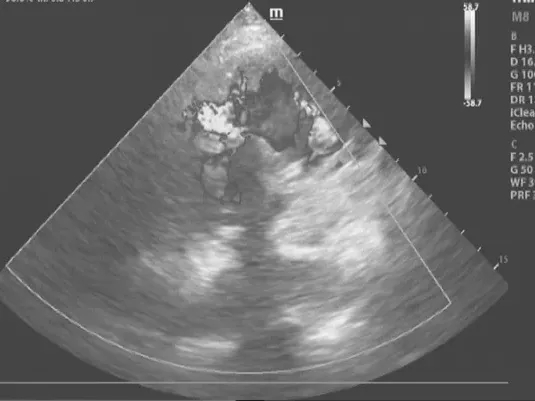

冠脉介入术后1周,在丁春华主任带领下,为患者实施经皮室间隔缺损封堵术。术中,团队凭借丰富经验与精准操作,在DSA(数字减影血管造影)引导下,封堵器被精准送达穿孔部位,并实现成功释放。经心脏超声检查阻断了心室间的异常分流,达到手术终点,患者自诉呼吸顺畅,胸闷症状立即缓解,整个手术过程历时1小时,全程生命体征平稳。

室间隔缺损封堵术后超声